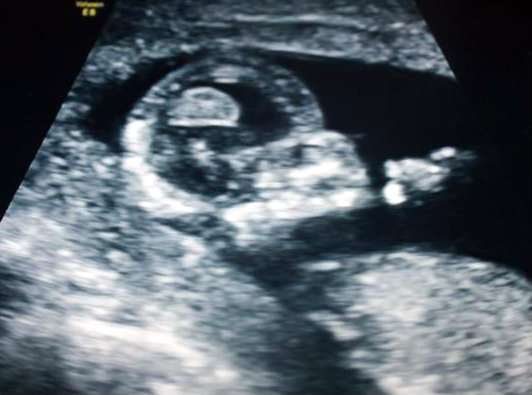

13 week ultrasound - can you see a nub? Lovemy4, please help! :)

I had an ultrasound yesterday at 12 weeks 5 days. Baby was measuring 13 weeks 3 days. Heart rate was 167. Baby was moving around a lot and I'm not sure if I ever saw a clear nub at all. :( I did see a potty shot and didn't see anything protruding between the legs at all, I saw what looked like a white spot between the legs (didn't see three lines, but wondering if it may have been girly parts seen from a distance, it wasn't a very close-up shot). My symptoms this pregnancy have been identical to my previous girl pregnancy. I don't have a gender preference, but this just feels like a girl to me. Any thoughts? If the nub isn't visible, what do you think based on skull shape? I thought the profile reminded me of my daughter, she had a rounded forehead like this, and my son's was very straight.